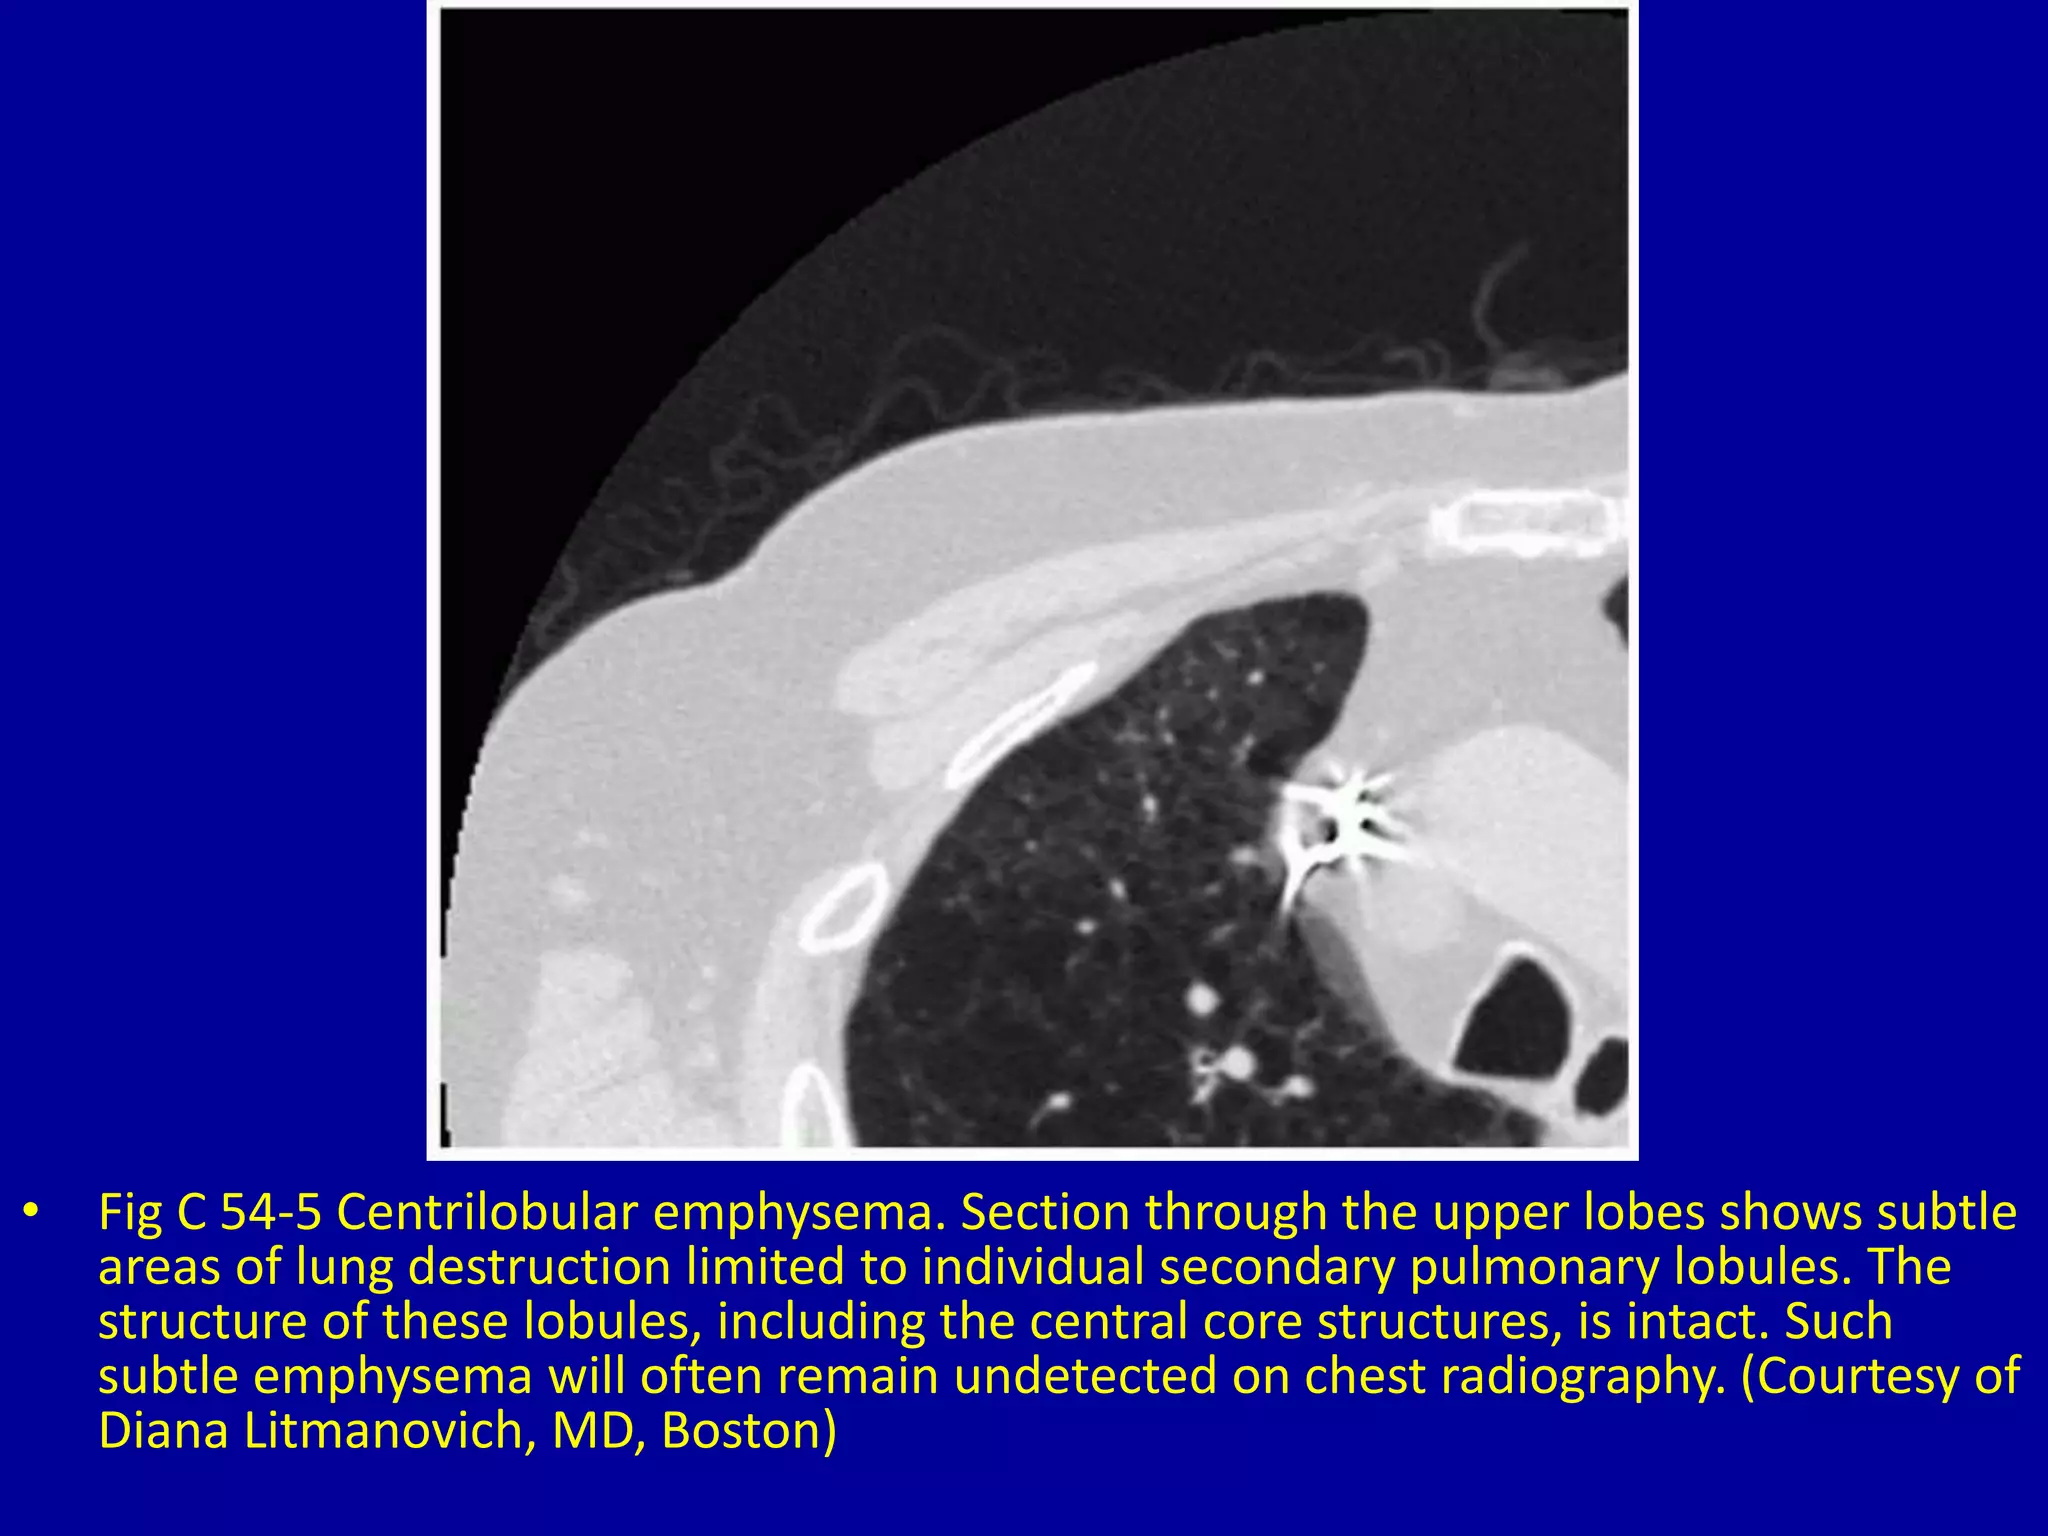

This document discusses various pulmonary diseases that predominantly affect the upper zones of the lungs. It includes 10 figures showing CT scan findings of different conditions like postprimary tuberculosis, sarcoidosis, pulmonary Langerhans cell histiocytosis, silicosis, centrilobular emphysema, chronic eosinophilic pneumonia, cystic fibrosis, allergic bronchopulmonary aspergillosis, neurogenic pulmonary edema, and ankylosing spondylitis. The images demonstrate lesions, nodules, consolidations, cysts, and other abnormalities that are largely limited to the upper lobes and regions of the lungs.